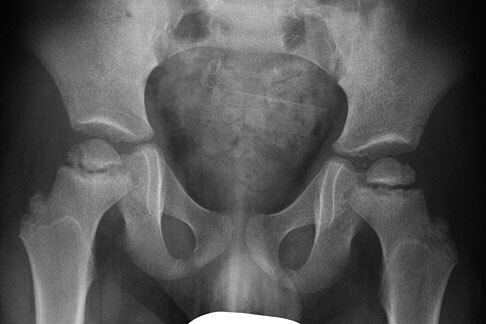

What is the radiographic classification system:

International Hip Dysplasia Institute classification system The location of the center of the proximal femur metaphysis in relation to the Hilgenreiner line (H-line), Perkin line (P-line), and an oblique line bisecting the lower/outer quadrant is shown. The H-line is drawn through the top of the tri-radiate cartilages bilaterally. The P-line is drawn perpendicular to the H-line at the superolateral margin of the acetabulum. The D-line is a diagonal line drawn 45° from the junction of the H-line and P-line. The H-point is the midpoint of the superior margin of the ossified metaphysis. Grade I, the H-point is at or medial to the P-line. Grade II, the H-point is lateral to the P-line and at or medial to the D-line. Grade III, the H-point is lateral to the D-line and at or inferior to the H-line. Grade IV, the H-point is superior to the H-line.